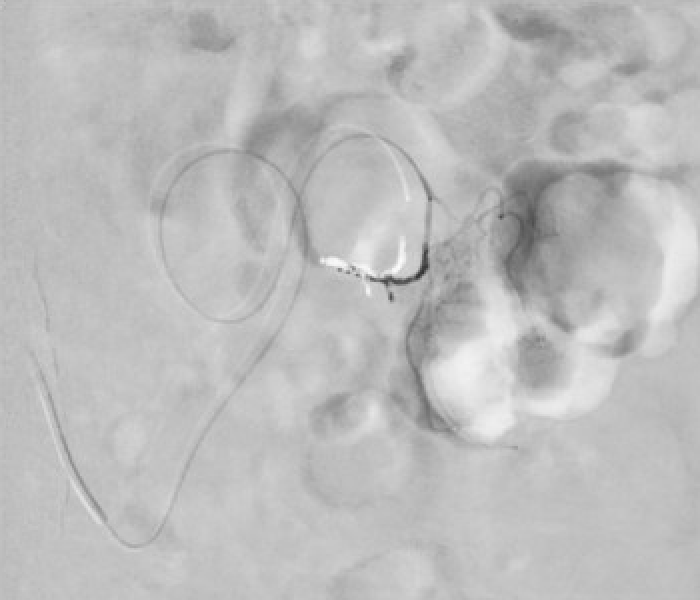

Embolization was performed with Penumbra LP coils through the 2.0 Fr ProGreat microcatheter. The intermittent bleeding stopped and the patient was discharged two days later.